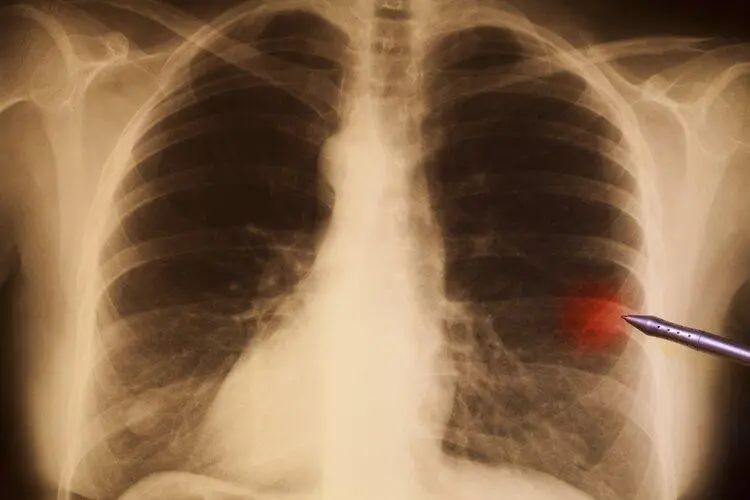

1、肺结节样钙灶化

上海市肺科医院呼吸内科副主任医师胡洋介绍:如果报告单上显示钙化结节、肺结节样钙化灶等字样,都无需处理,这些多数疾病恢复后的疤痕,不会影响肺功能。